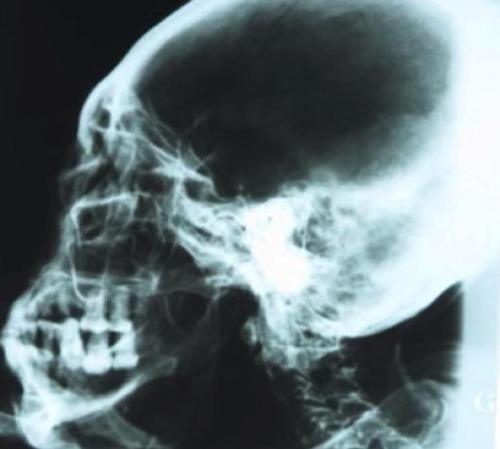

Мумия похожа на гипсовую скульптуру, посыпана каким-то белым порошком. Но, как показал рентген и компьютерная томография, это отнюдь не изваяние. Внутри — скелет, останки внутренних органов. Посредством радиоуглеродного анализа установлено, что тканям мумии 2300 — 2500 лет . Порошок, по мнению ученых, обладает бальзамирующими свойствами. Мумия обсыпана им для сохранности.

Изображение мумии, полученное с помощью томографа

Рентгеновский снимок черепа мумии